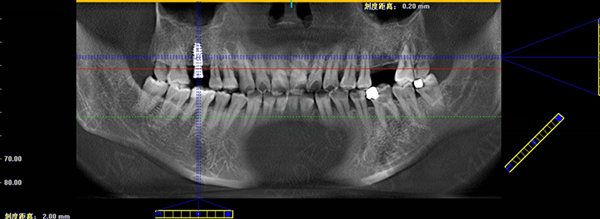

种牙完成后口腔ct全景片